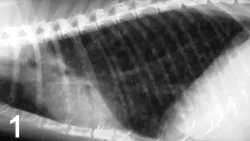

These changes are associated with cellular infiltration of the bronchial mucosa and submucosa. This tissue may also become edematous. See Figures 2 and 3.

F__igure 2. A cross section from the large airway of a cat with asthma, demonstrating the classic findings of smooth muscle hypertrophy,

invagination of epithelium (bronchoconstriction), and luminal exudate.